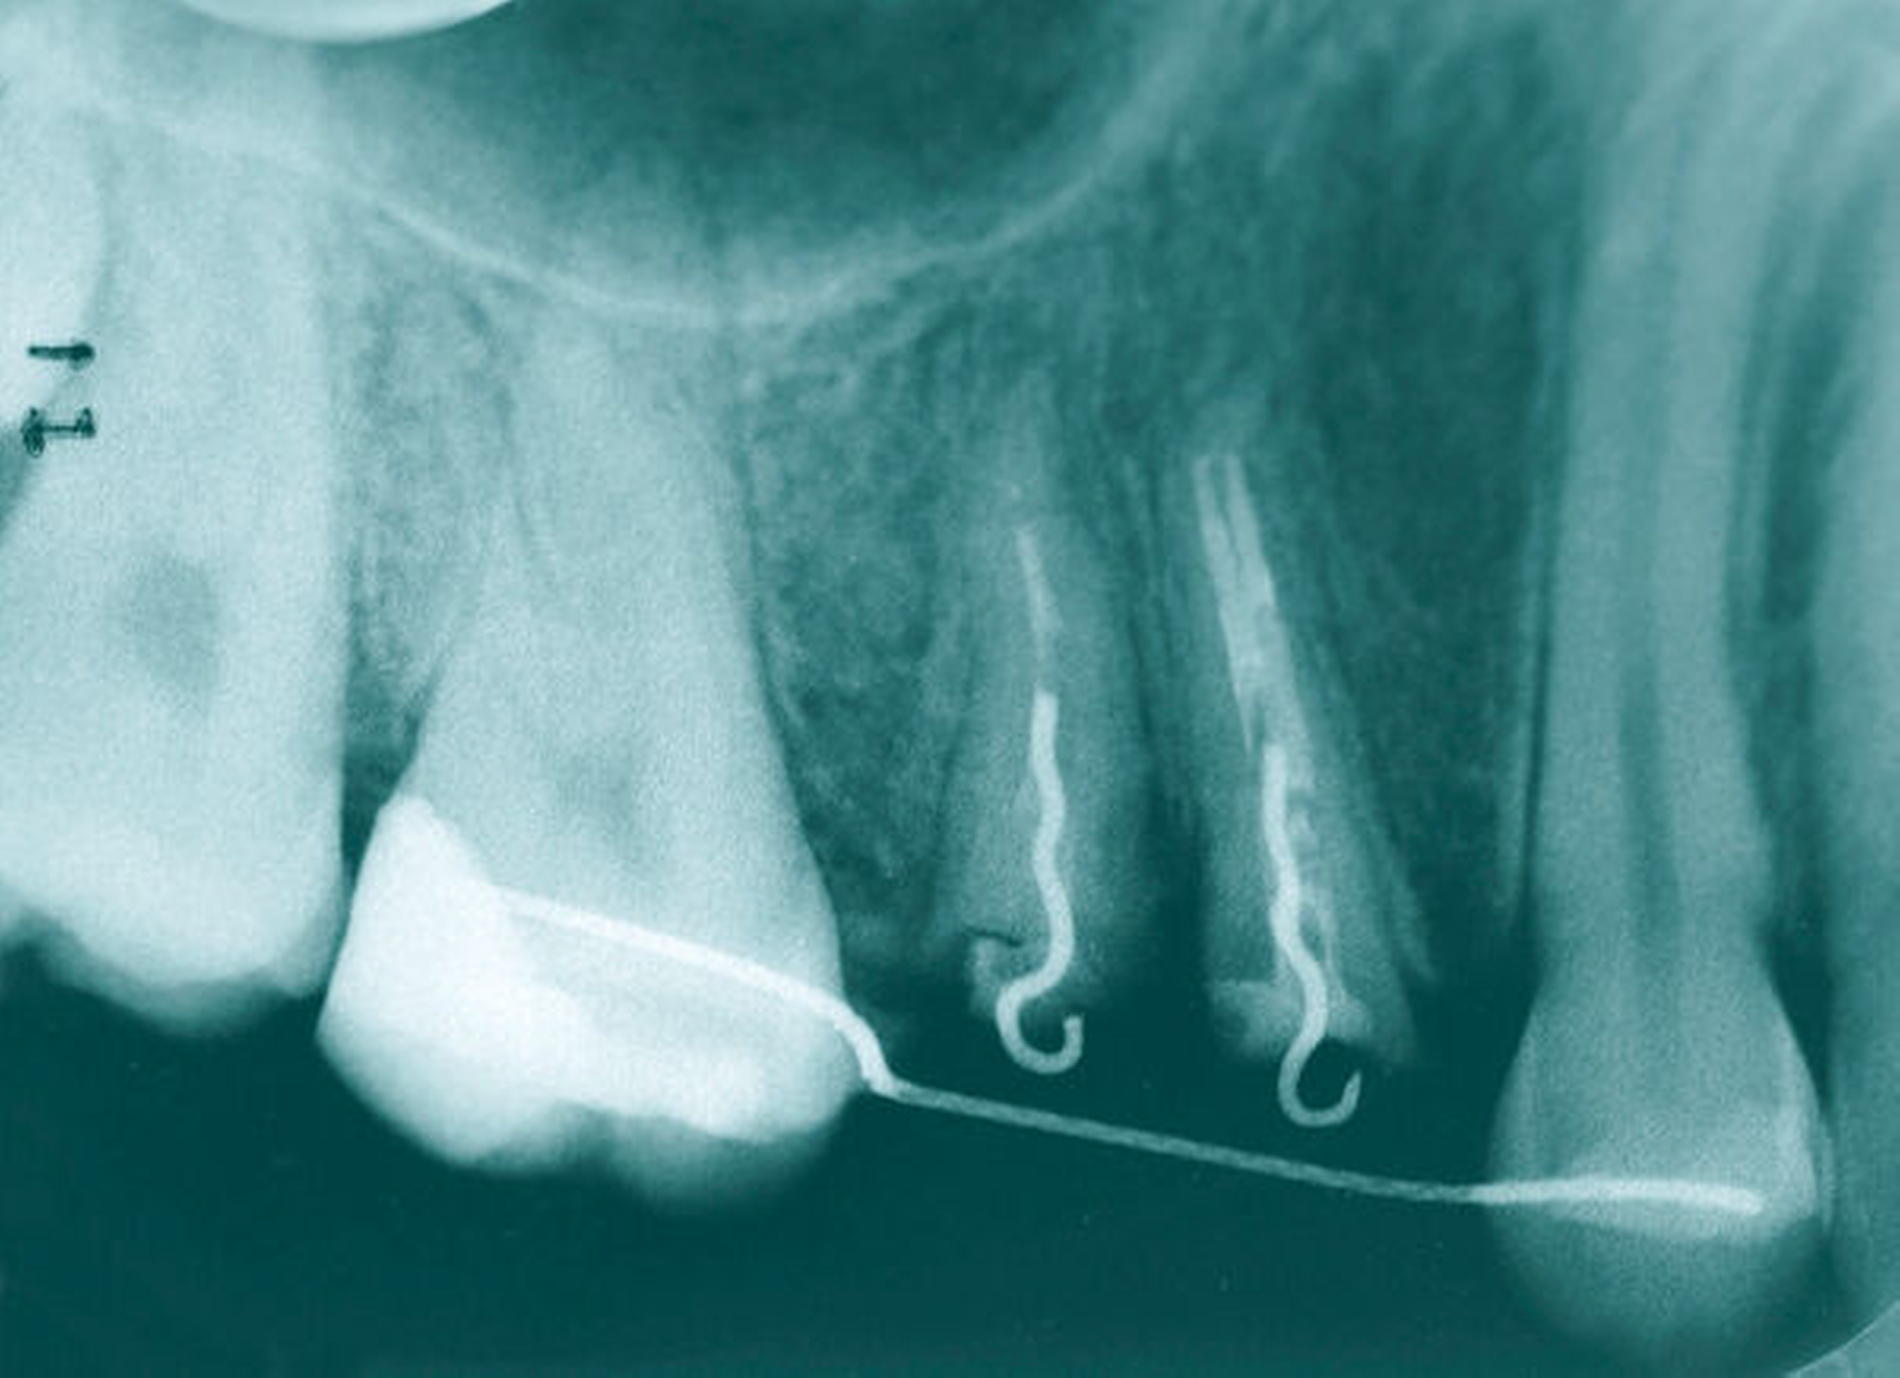

Nach der endodontischen Behandlung der Zähne 14 und 15 erfolgte die chirurgische Entfernung des mobilen vestibulären beziehungsweise oralen Kronenfragments sowie der infragingival frakturierten Wurzelanteile. In der gleichen Sitzung erfolgte die Aufklappung vestibulär und oral, um nach Trocknung der Zahnstümpfe eine adhäsive Befestigung von zuvor auf dem Modell gefertigten Drahtschlaufen (018``Stahl: Dentalline, Deutschland) zu ermöglichen. Diese wurden mittels dual härtendem Composit (Rebilda DC, Voco) intrakanalär verankert. Mithilfe eines weiteren, an den mesialen und distalen Nachbarzähnen adhäsiv angebrachten Drahtes (17x25 TWIST, 3-fach verseilt; Dentalline, Deutschland) und einer elastomeren Kette (Energy Chain, Rocky Mountain Orthodontics, USA) war es nun möglich, die Wurzelreste orthodontisch aus den Alveolen zu extrudieren. Hierzu waren über einen längeren Zeitraum mehrere Behandlungstermine nötig, bei denen die Gummizüge entsprechend des Behandlungsfortschritts gewechselt wurden. Des Weiteren erfolgten in regelmäßigen Abständen Inzisionen im PA-Spalt, um eine Mitwanderung des Knochens zu vermeiden. Anders als bei festsitzenden Multibandapparaturen ist eine definitive Kraftangabe bezüglich der Extrusion nicht möglich, da sich die Kräfte mit fortschreitendem Extrusionsgrad und je nach verwendeter elastomerer Kette ändern.

Auf eine provisorische Versorgung zur Kaschierung der fehlenden Zahnkronen musste in der Zeit verzichtet werden. Dies wurde von der Patientin akzeptiert. Gleichwohl war die Patientin sehr froh, als nach zehn Monaten die Wurzeln mit 4 mm so weit nach crestal extrudiert schienen, dass nach einer anschließenden viermonatigen Retentionsphase die provisorische Versorgung erfolgen konnte. Zwischenzeitlich wurde Zahn 15 revidiert, da die endodontische Versorgung initial, aufgrund der Fragmente und somit ungenauer endometrischer Längenbestimmung, nicht exakt genug erfolgen konnte und die Vorraussetzungen vor der weiteren Versorgung möglichst optimiert werden sollten. Anschließend wurden beide Zähne mit adhäsiven Stiften (Komet) und Aufbaufüllungen (Optibond FL, (Kerr); Rebilda DC, (Voco)) versorgt und für die Aufnahme der LZPV-Kronen präpariert. Es erfolgte eine langzeitprovisorische Versorgung mit verblockten, laborgefertigten Kunststoff Provisorien (Dentallabor Wehner, Ludwigshafen).

Auch bei scheinbar nicht optimalen Grundvoraussetzungen – wie einem zu erwartenden nicht ganz idealen Kronen-Wurzel-Verhältnis (1:1) – scheint die kieferothopädische Extrusion als Behandlungsoption nicht direkt ausgeschlossen werden zu müssen. Auf dem im Fall gezeigten OPG (Abbildung 9) stellen sich die Zahnwurzeln von 14 und 15 im kontralateralen Vergleich deutlich kürzer dar als die der Zähne 24 und 25. Die elektronische Messlänge bei der Revision der endodontischen Behandlung von Zahn 15 vor Eingliederung des Langzeitprovisoriums betrug lediglich 12 mm. Dennoch wiesen die Zähne 14 und 15 nach der Retentionsphase keine Lockerungsgrade auf, sodass die Autoren in der vermeintlich geringen Wurzellänge keine unbedingte Kontraindikation für das Ziel der Zahnerhaltung sehen. Auch wenn in diesem Fall die unterschiedliche Zahnlänge der Prämolaren im kontralateralen Vergleich klar mit der Extrusion der Zähne 14 und 15 zu erklären ist, stellen kieferorthopädische Bewegungen auch eine mögliche Ursache für die Verkürzung von Zahnwurzeln durch Resorptionen dar.